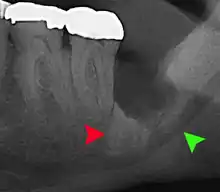

Impacted 2nd molar (red arrow) with developing wisdom tooth (green arrow)

There is no standard to screen for wisdom teeth. It has been suggested, absent evidence to support routinely retaining or removing wisdom teeth, that evaluation with panoramic radiograph, starting between the ages of 16 and 25 be completed every 3 years. Once there is the possibility of the teeth developing disease, then a discussion about the operative risks versus long-term risk of retention with an oral and maxillofacial surgeon or other clinician trained to evaluate wisdom teeth is recommended. These recommendations are based on expert opinion level evidence.[19] Screening at a younger age may be required if the second molars (the "12-year molars") fail to erupt as ectopic positioning of the wisdom teeth can prevent their eruption. Radiographs can be avoided if the majority of the tooth is visible in the mouth.